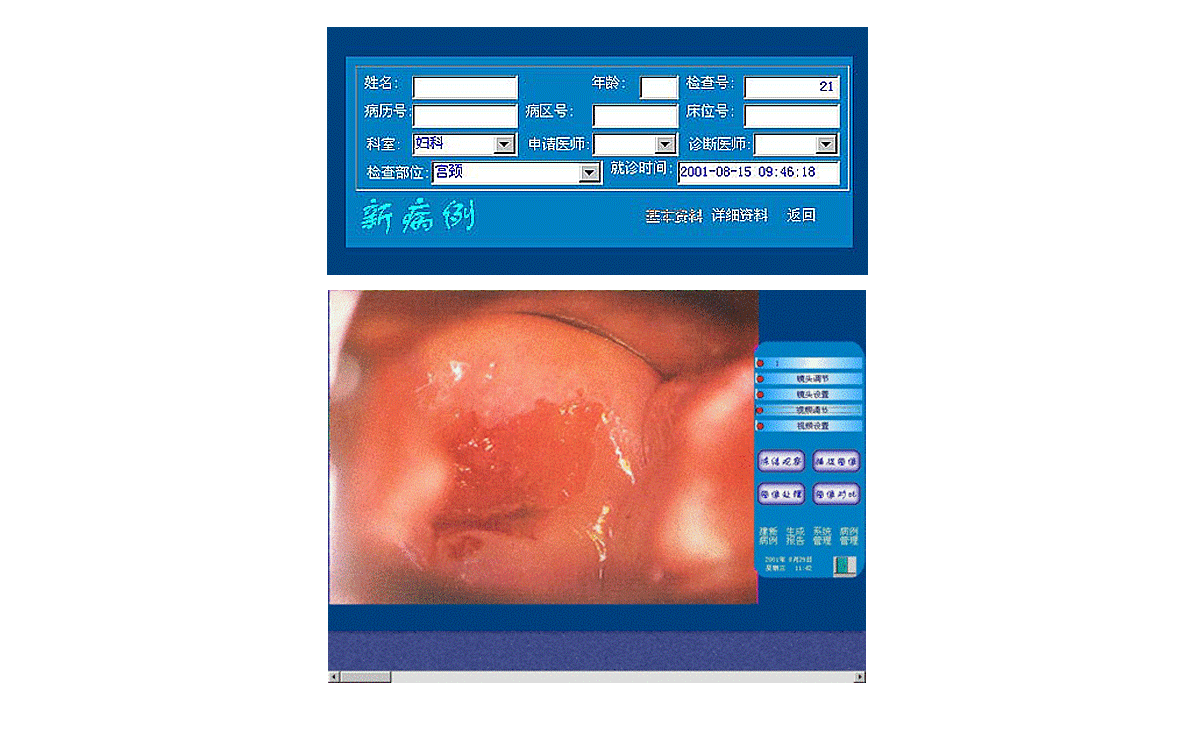

3、打開(kāi)顯視器電源開(kāi)關(guān),開(kāi)啟主機(jī)電源總開(kāi)關(guān),開(kāi)啟陰道鏡系統(tǒng),待系統(tǒng)進(jìn)入正常窗口界面后,先創(chuàng)建新病例,通過(guò)觀察、采集、生成報(bào)告后,即可完成整個(gè)陰道鏡檢查與診斷操作。

2、用鼠標(biāo)點(diǎn)擊主界面窗口中<建新病例>按鈕后輸入病人的一些資料,再點(diǎn)擊該窗口上的<返回>按鈕,系統(tǒng)進(jìn)入圖像采集窗口界面,這時(shí)圖像采集窗口將顯示陰道鏡所觀察到的動(dòng)態(tài)影像。